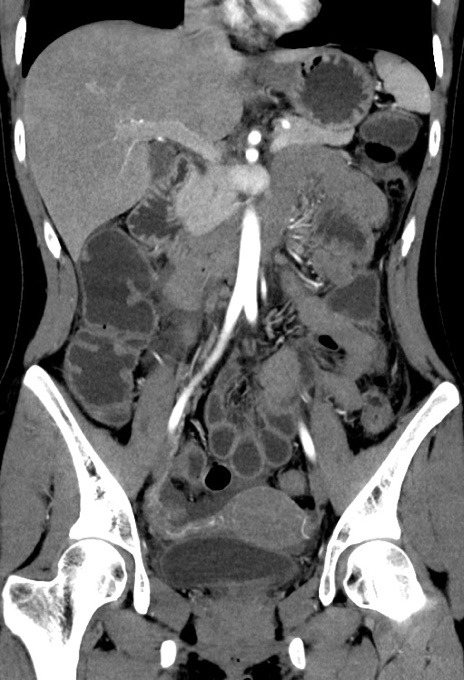

症例17(冠状断像)

【症例】20歳代女性

【主訴】嘔吐、下腹部痛

【現病歴】昨日夕食後に嘔吐し下腹部痛が出現。本日になっても嘔吐持続し改善しないため来院。

【身体所見】意識清明、BT 37.2℃、BP 108/67mmHg、腹部:平坦、やや硬、下腹部正中から右にかけて圧痛あり、反跳痛軽度あり、tapping pain(+)。

【データ】WBC 13600、CRP 14.94